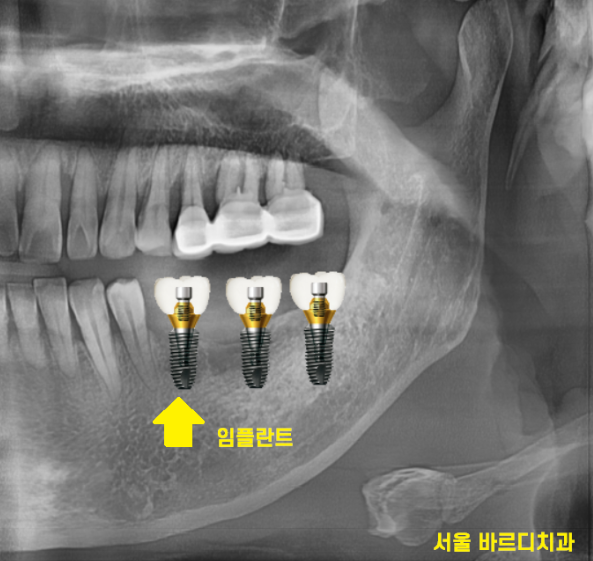

230921

상일동역 치과 수술 직후의 사진입니다.

사진을 보시면 나사가 하나 들어간 것을

확인하실 수 있는데요.

221123

때문에 임플란트 수술을 하고 나면

머리 대신에 작은 나사만 연결해둡니다.

뼈가 거의 없는 경우에는

임플란트를 잇몸 안에 묻어두기도 하는데요.

이럴 경우에는 잇몸밖에 안느껴지기 때문에

임플란트 심은게 맞나.. 싶기도 합니다.

230707

겉으로 봤을 때는 잇몸만 느껴지지만

x-ray를 보실까요~?

230717

임플란트가 잘 심어져있습니다.